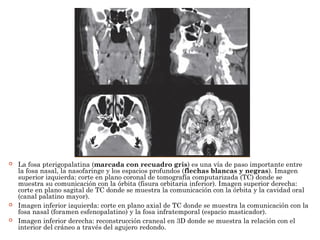

 La fosa pterigopalatina (marcada con recuadro gris) es una vía de paso importante entre

la fosa nasal, la nasofaringe y los espacios profundos (flechas blancas y negras). Imagen

superior izquierda: corte en plano coronal de tomografía computarizada (TC) donde se

muestra su comunicación con la órbita (fisura orbitaria inferior). Imagen superior derecha:

corte en plano sagital de TC donde se muestra la comunicación con la órbita y la cavidad oral

(canal palatino mayor).

 Imagen inferior izquierda: corte en plano axial de TC donde se muestra la comunicación con la

fosa nasal (foramen esfenopalatino) y la fosa infratemporal (espacio masticador).

 Imagen inferior derecha: reconstrucción craneal en 3D donde se muestra la relación con el

interior del cráneo a través del agujero redondo.